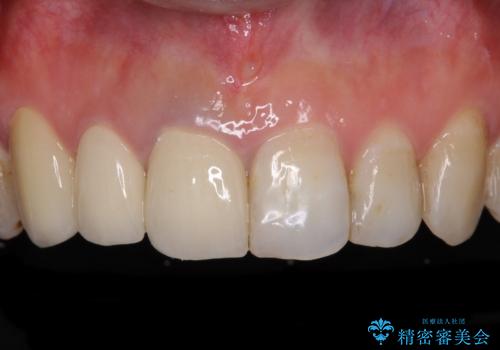

- 前歯の歯並びやむし歯治療の跡、奥歯の銀歯を気にして来院された患者様です。

インビザラインによる矯正治療の後に虫歯や銀歯をセラミックにて補綴することとしました。

前歯のむし歯治療の跡や奥歯の目立つ銀歯がなくなり、明るい口元になりました。